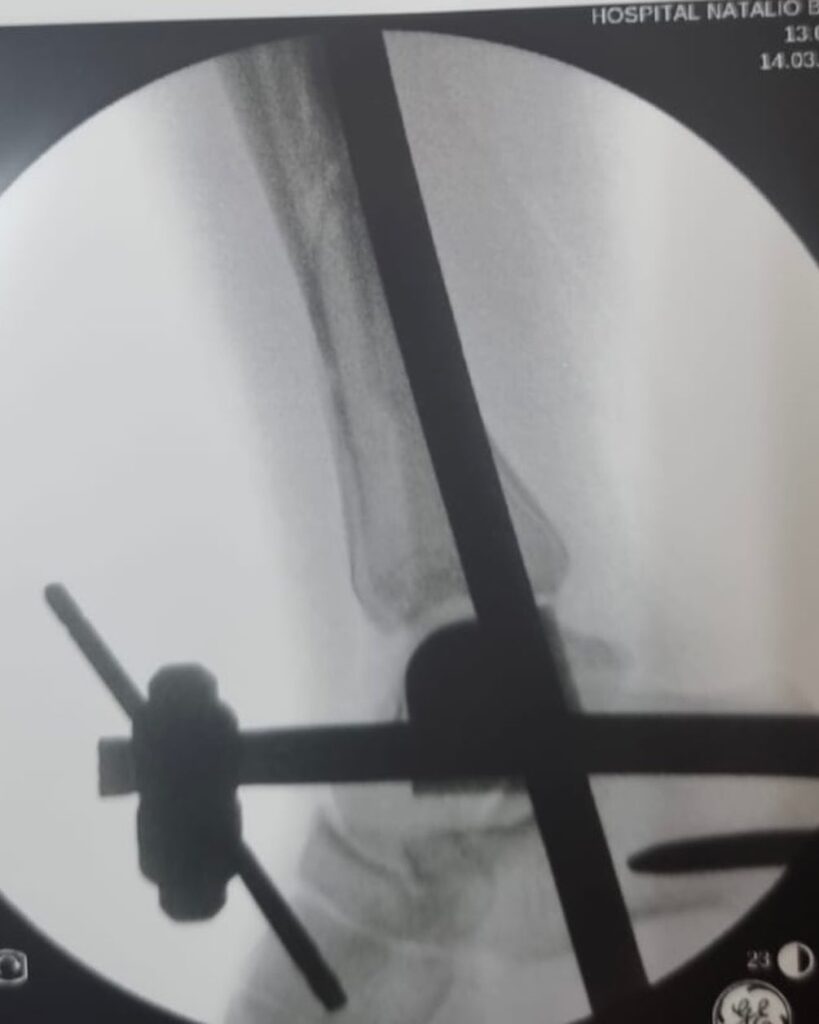

El manejo inicial de una fractura compleja de tibia representa un punto de inflexión en el proceso de recuperación del paciente. Tal como lo destacó el Dr. Escobar, la fijación externa emerge como una herramienta invaluable en esta etapa crítica.

- Estabilización inmediata: Al unir los fragmentos óseos de manera externa, se proporciona una estabilidad que reduce el dolor, disminuye el riesgo de complicaciones vasculares y nerviosas, y mejora el pronóstico de las partes blandas.

- Facilita la cirugía definitiva: La fijación externa permite abordar la fractura de manera más controlada y precisa en una segunda intervención. Al reducir el edema y la inflamación, se facilita la exposición quirúrgica y se minimizan las complicaciones intraoperatorias.

- Versatilidad: La fijación externa puede adaptarse a una amplia variedad de fracturas, permitiendo modular la carga y el movimiento según las necesidades del paciente.

La elección del tipo de fijador externo y el protocolo de tratamiento dependerán de diversos factores, como la localización y gravedad de la fractura, el estado de las partes blandas y las condiciones generales del paciente. Es fundamental que la decisión sea tomada de manera multidisciplinaria, involucrando al traumatólogo, el cirujano ortopédico y otros especialistas según sea necesario.